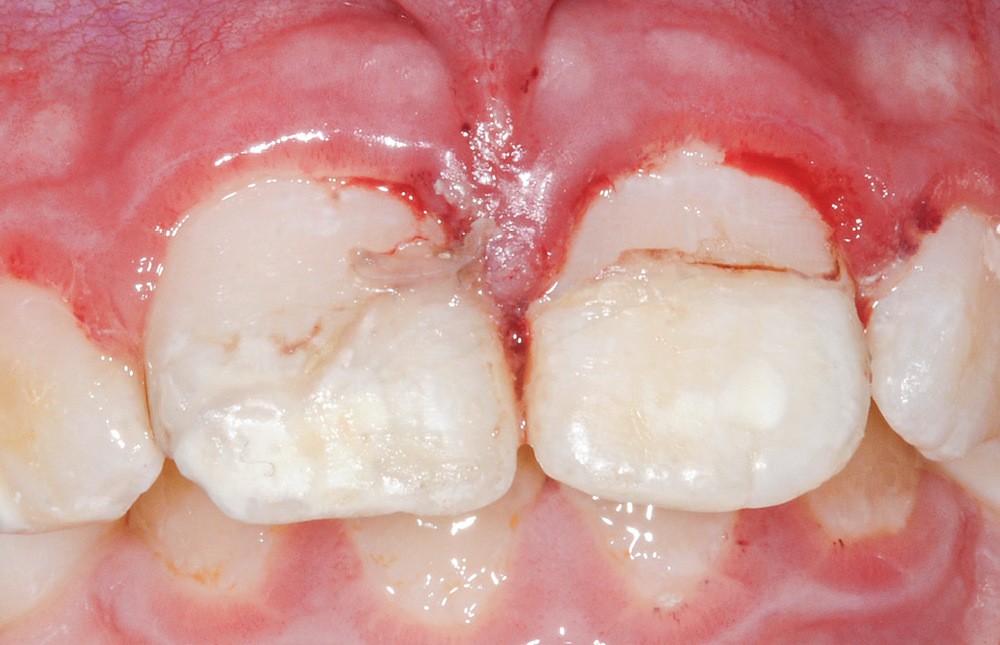

Tous ces examens se révèlent négatifs. Nous procédons donc à l’examen de la sphère orale qui objective :

- une plaie au niveau du frein labial supérieur ;

- une fracture corono-radiculaire avec effraction pulpaire de 11 et 21 (fig. 1 et 2) ;

- une subluxation de 11 et 21 (saignements sulculaires).

La présence d’une hypominéralisation molaire-incisive (MIH) est notée, car 16 et 36 présentent des opacités beiges et jaune brun.